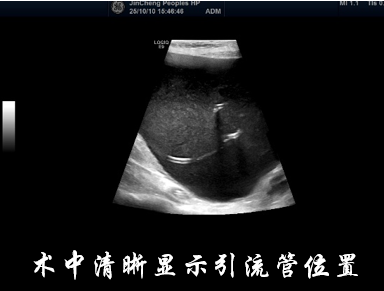

治疗第一步是穿刺引流减压。张奶奶取平卧位,医护人员对手术区域进行常规消毒铺巾后,用1%利多卡因进行局部麻醉。随后,在超声的实时引导下,将一次性8.5F PTCD引流管精准置入囊腔内,缓慢间断地引出囊液约2000ml,相当于4瓶矿泉水的量。引流结束后,张奶奶当即感觉腹痛、腹胀症状明显缓解,当天进食量就有所增加。

为彻底破坏囊肿囊壁,防止复发,团队并未急于求成,而是根据囊腔大小和张奶奶的耐受情况,分阶段进行硬化治疗。10月14日,首次在超声引导下进行酒精与聚桂醇联合硬化治疗,张奶奶没有出现明显不适。第二天张敬强主任医师查房时,她高兴地说:“吃饭香了,也不怎么疼了。”